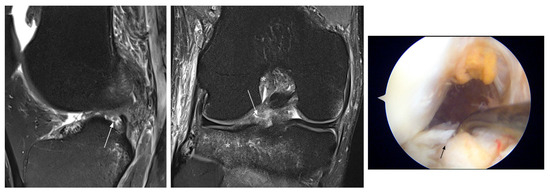

| Interpretation | ||||||

| FN MM | ||||||

| 16 | M, 45 y | 80 | missed peripheral tear posterior horn | unstable tear posterior horn | chronic | R |

| 17 | M, 40 y | 10 | missed posterior root tear | oblique root tear | acute | R |

| FN LM | ||||||

| 18 | M, 48 y | 50 | missed posterior root tear | posterior root tear | acute | R |

| 19 | F, 41 y | 9 | missed tear posterior horn | unstable tear posterior horn | acute | PM |

| 20 | M, 36 y | 30 | missed posterior root tear | partial posterior root tear | acute | R |